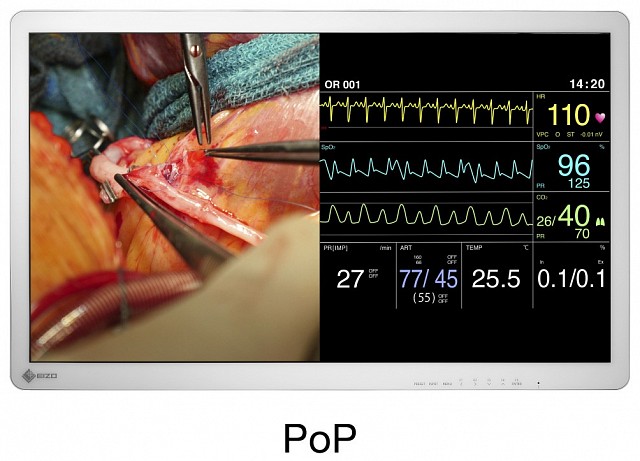

具有4K UHD(3840 x 2160像素)分辨率和高亮度的32英寸宽屏手术监视器。

EX3241具有4K UHD(3840 x 2160像素)分辨率和高亮度的32英寸宽屏手术监视器。

输入端口切换、亮度、灰阶曲线、色域等各种设置,都可以作为预设功能存储在监视器中。可以根据用户的偏好通过屏幕菜单来命名这些设置。